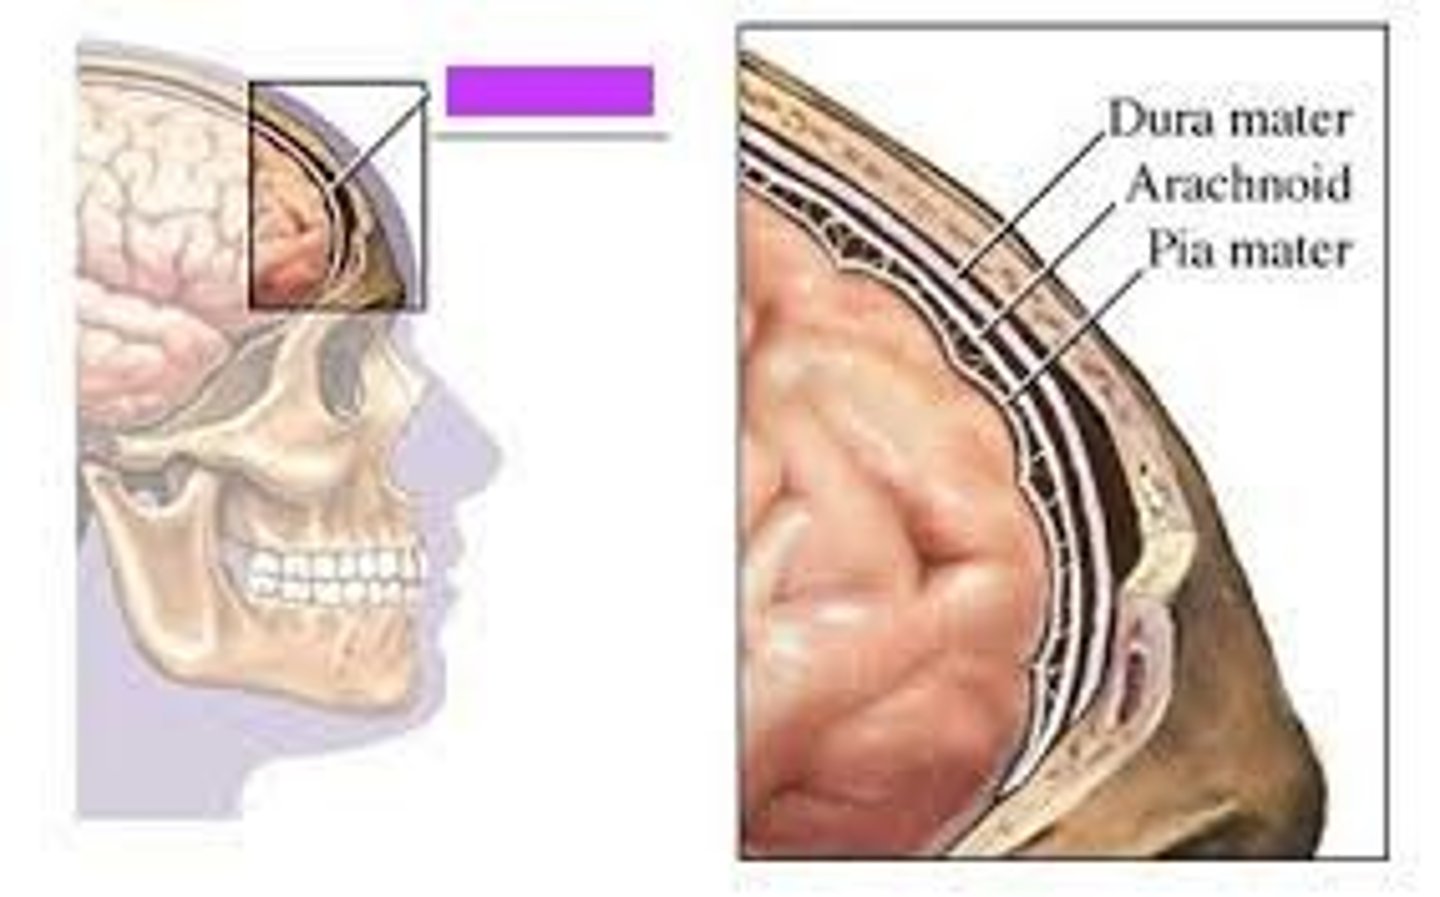

Meninges

-Three connective tissue membranes that envelope the CNS

-Protect the CNS and provide structural framework for its arteries and veins

Meninges Location

-Lies between the nervous tissue and bone

Cranial dura mater

-Outer periosteal

-Inner meningeal

-Folds inward to extend between parts of the brain

Cranial dura mater location

-Layers separated by dural sinuses

-Pressed closely against cranial bones

=No epidural space

=Only attached to bone around foramen magnum, stella turcica, crista galli, and sutures of the skull

Periosteal

-Equivalent to periosteum of cranial bones

Meningeal

-Continuous into vertebral canal and forms dural sheath around spinal cord

Dural sinuses

-Separates layers of cranial dura mater

-Collect blood circulating though brain

Arachnoid mater

-Transparent membrane over brain surface

Subarachnoid space

-Separates arachnoid mater from pia mater below

-Contains CSF

Subdural space

-Separates arachnoid from dura mater above in some spaces

Pia mater

-Very thin membrane that follows contours of brain, even dipping into sulci

-Not usually visible without a microscope